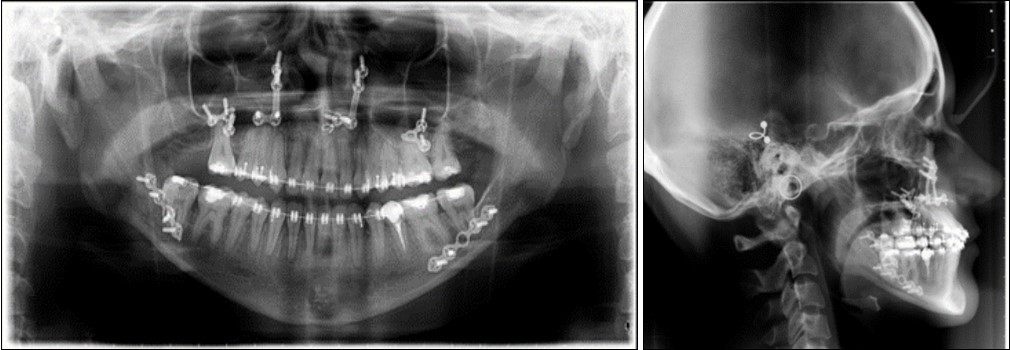

The panoramic radiograph examination showed impacted bilateral mandibular third molars, and one maxillary third molar.Cephalometric analysis disclosed a skeletal class III (ANB -5 degrees), with a retruded maxilla and a protruded mandible (SNA 78 degrees and SNB 83 degrees). The patient is a hyperdivergent type, with FMA 30 degrees and IMPA 77 degrees, which suggests retruded lower incisors. Examination of soft tissue on the profile radiograph shows a concave profile and a protruded lower lip. (Figure 3).

Figure 3.Initial panoramic and lateral cephalometric radiographs

Initial panoramic and  lateral cephalometric radiographs

Post-surgical orthodontic treatment was started 4 weeks after the surgery. Wearing of bilateral box elastics was recommended in order to improve interdigitation. (Figure 6) The orthodontic treatment was finished on 0.019x0.025 SS archwires. Post-surgery cephalometric analysis revealed an increase in SNA value by 4 degrees (SNA 82 degrees) and a decrease in SNB value also by 4 degrees (SNB 79 degrees). The patient was now in a skeletal class I, with ANB 3 degrees. An examination of the soft tissue on the radiograph reveales a better relation between the upper and lower lip. (Figure 7).

Figure 7.Post-surgical panoramic and lateral cephalometric radiograph.

Post-surgical panoramic and lateral cephalometric radiograph.